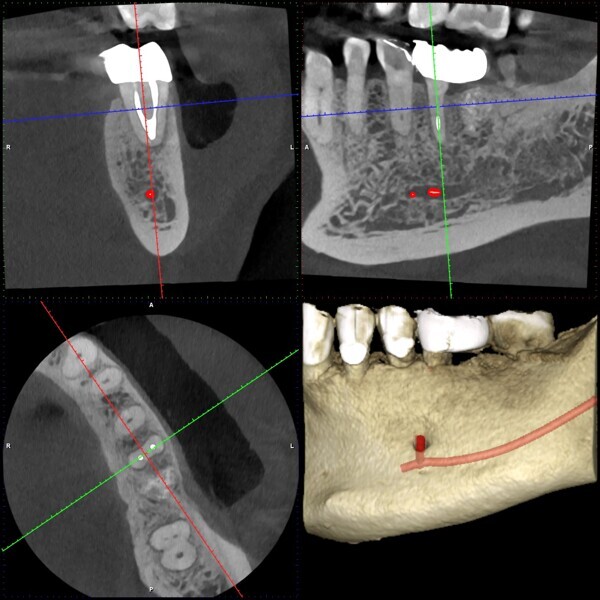

One year later, the restoration was performing well and the patient was asymptomatic. Radiographs and a CBCT control scan showed complete bone healing. On the periapical radiograph, the tooth showed a healthy periodontal ligament and no signs of failure in the restoration (Fig. 12). The cross-sectional, axial and coronal views of the CBCT scan showed good bone width and height and no pathological findings (Figs. 13–16). The oclusal scans and clinical images showed good adaptation of the new restoration and a healthy gingiva (Figs. 17–20).